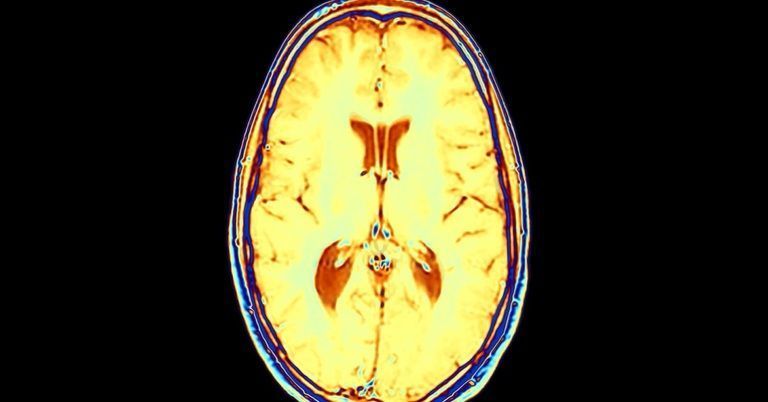

Forscher lüften Corona-Geheimnis: So kommt das Virus ins Gehirn

Wissenschaftler des Instituts Pasteur in Paris sind nun der Frage nachgegangen, wie das Coronavirus in die Gehirnzellen hineinkommt.